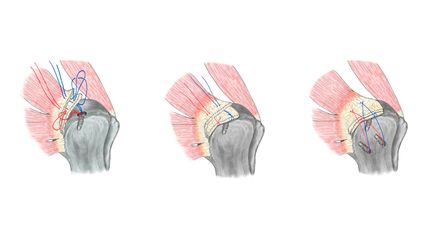

Alle Patient:innen wurden von 2 Senior-hauptoperateuren über einen posterioren Zugang operiert, aus hygienischen Gründen wurden keine vorderen Zugänge angewandt. Bei vielen Patient:innen sind Pilzerkrankungen in der Leiste zu beobachten, daher sollte der Zugang nach Meinung der Autoren einen möglichst grossen Abstand von der Leiste haben. Dies wird durch eine Publikation von Watts untermauert, der eine deutlich geringere Infektionsrate beim posterolateralen Zugang im Vergleich zum anterioren Zugang beschrieben hat.12 Alle Prothesenpfannen wurden zementfrei verankert, 6 Patient:innen erhielten eine Double-Mobility-Pfanne. Die Arbeitsgruppe von Hernigou hat bei sehr adipösen Patient:innen eine Reduktion der Luxationsrate von 21,8% auf 2,8% durch Verwendung von Double-Mobility-Pfannen erreichen können.13 12 Patient:innen wurden mit zementfreien Femurkomponenten versorgt.